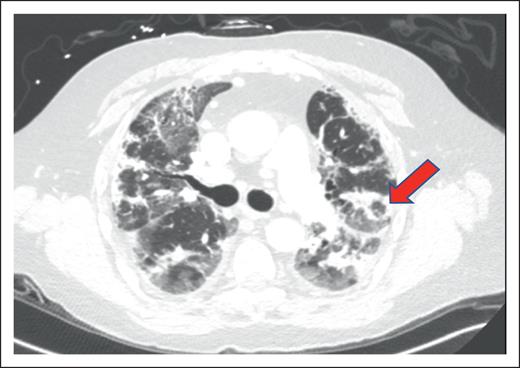

Radiological appearance of HCT-OP can be diverse, ranging from the classic atoll sign (Figure 2) to a combination of nonspecific ground-glass opacities and consolidation in peribronchovascular or subpleural distribution, with or without architectural distortion of the lung, resulting from fibrosis.19 HCT-OP can occur either unilaterally or bilaterally, as a single lesion or with multifocal consolidations without zonal preference.20,33 Rarely, HCT-OP may present as distinct nodular consolidation.34 If the clinical history and radiographic history are highly suggestive of HCT-OP and infectious workup is unrevealing, treatment for HCT-OP should be initiated.

Figure 2.

Example of HCT-OP on CT scan of the chest. Noncontrast axial CT image, demonstrating multifocal consolidative and ground-glass pulmonary opacities. The atoll sign (arrowhead) can occasionally be seen and is characterized by central ground-glass opacity surrounded by dense consolidation, representing perilobular involvement, known as the reversed halo sign. Involvement in this case is predominantly peripheral, but HCT-OP can also be peribronchovascular, or occasionally nodular.